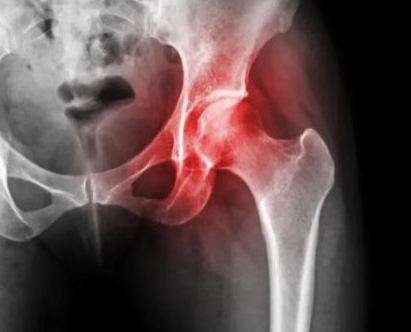

股骨头坏死的核心诱因是股骨头血供不足,导致骨细胞缺血、坏死、骨小梁塌陷。其早期信号并非剧烈疼痛,反而具有一定隐蔽性。最典型的表现是髋部隐痛或酸痛,疼痛部位多在腹股沟区、臀部深处,部分人会出现大腿内侧或膝关节内侧放射性疼痛,容易误判为膝关节问题。这种疼痛初期多在活动后加重,休息后可缓解,夜间睡眠时可能轻微隐痛,常被误认为“劳累过度”。

随着病情发展,信号会逐渐明显。患者可能出现髋关节活动受限,比如穿袜子、系鞋带时,髋关节外展、旋转动作不灵活;走路时感觉髋部有卡顿感,轻微活动后可缓解。部分人会伴随走路跛行,初期可能仅在长时间行走后出现,休息后恢复正常,后期跛行症状会逐渐加重,这是由于股骨头受力能力下降,身体本能调整步态导致。